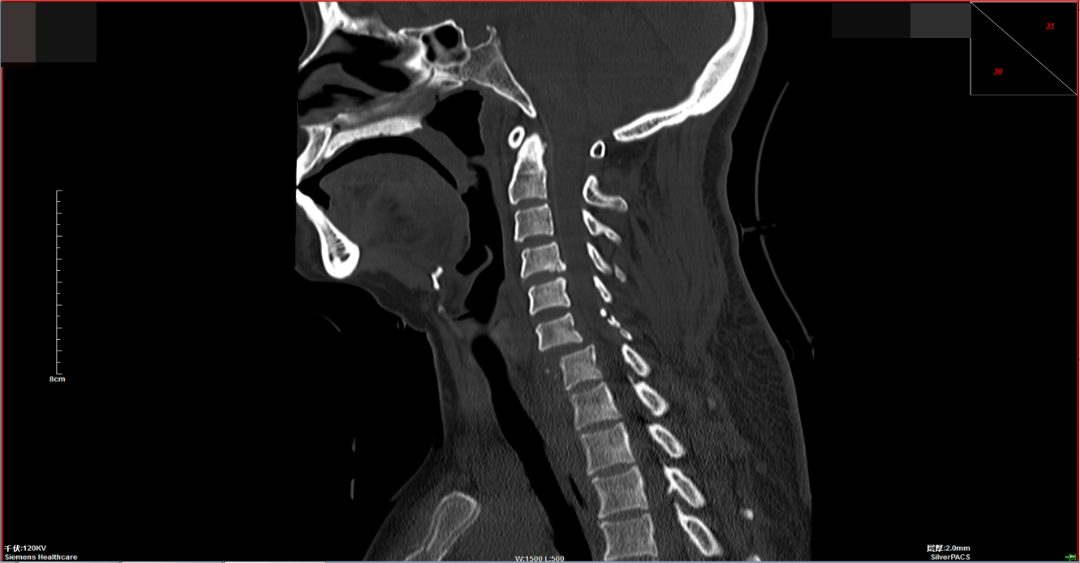

近日,市民羅阿姨在家中爬樹摘龍眼時(shí)不慎墜落,導緻頸部疼痛且四肢不能(néng)活動,由家人送往外院就(jiù)診行頸椎CT提示頸6/7椎體骨折脫位,患者家屬爲求進(jìn)一步手術治療,于是到惠州六院脊柱外科就(jiù)診。

脊柱外科值班醫師接診病人後(hòu)診斷羅阿姨是頸椎骨折脫位并脊髓損傷,合并四肢癱,随後(hòu)醫師爲患者行顱骨牽引治療。針對(duì)羅阿姨的情況,脊柱外科團隊進(jìn)行讨論後(hòu)一緻認爲患者目前四肢肌力0級,胸骨角平面(miàn)以下感覺喪失,鑒于脊髓損傷恢複難度大,卧床并發(fā)症多,最佳治療措施是行頸椎骨折脫位切開(kāi)複位椎弓根螺釘内固定+椎闆切除椎管擴大減壓術。